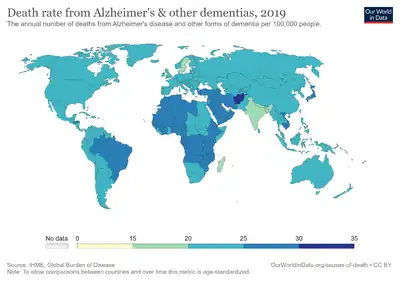

In 2015, there were approximately 29.8 million people worldwide with AD.[2][8] It most often begins in people over 65 years of age, although 4–5% of cases are early-onset Alzheimer's.[3] It affects about 6% of people 65 years and older.[1] In 2015, dementia resulted in about 1.9 million deaths.[9] It was first described by, and later named after, German psychiatrist and pathologist Alois Alzheimer in 1906.[18] In developed countries, AD is one of the most financially costly diseases.[19][20]

Two main measures are used in epidemiological studies: incidence and prevalence. Incidence is the number of new cases per unit of person–time at risk (usually number of new cases per thousand person–years); while prevalence is the total number of cases of the disease in the population at any given time.

Regarding incidence, cohort longitudinal studies (studies where a disease-free population is followed over the years) provide rates between 10 and 15 per thousand person–years for all dementias and 5–8 for AD,[218][219] which means that half of new dementia cases each year are AD. Advancing age is a primary risk factor for the disease and incidence rates are not equal for all ages: every five years after the age of 65, the risk of acquiring the disease approximately doubles, increasing from 3 to as much as 69 per thousand person years.[218][219] There are also sex differences in the incidence rates, women having a higher risk of developing AD particularly in the population older than 85.[219][220] In the United States, the risk of dying from Alzheimer's disease is 26% higher among the non-Hispanic white population than among the non-Hispanic black population, whereas the Hispanic population has a 30% lower risk than the non-Hispanic white population.[221]

Prevalence of AD in populations is dependent upon different factors including incidence and survival. Since the incidence of AD increases with age, it is particularly important to include the mean age of the population of interest. In the United States, Alzheimer prevalence was estimated to be 1.6% in 2000 both overall and in the 65–74 age group, with the rate increasing to 19% in the 75–84 group and to 42% in the greater than 84 group.[222] Prevalence rates in less developed regions are lower.[223] The World Health Organization estimated that in 2005, 0.379% of people worldwide had dementia, and that the prevalence would increase to 0.441% in 2015 and to 0.556% in 2030.[224] Other studies have reached similar conclusions.[223] Another study estimated that in 2006, 0.40% of the world population (range 0.17–0.89%; absolute number 26.6 million, range 11.4–59.4 million) were afflicted by AD, and that the prevalence rate would triple and the absolute number would quadruple by 2050.[225]